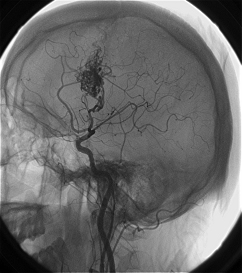

7、選擇性全腦血管造影(DSA)可了解AVM的部位、供血動脈、畸形血管團大小以及引流靜脈,了解是否伴有動脈瘤、靜脈瘤、動靜脈瘺及腦盜血情況。必要時加做頸外動脈造影,以了解是否有頸外動脈參與供血。

⑥腦血管造影。是診斷動靜脈畸形的重要手段。是必須進行的檢查方法。不僅能確定診斷而且還為治療提供依據。造影常顯示不規則曲張扭纏的畸形血管團,並可顯示供血動脈和引流靜脈。引流靜脈常在動脈期即可過早顯影。但仍有一部分小的或隱匿型動靜脈畸形不能被造影發現(約11%)。數字減影、放大造影、連續攝片、立體血管造影等更有助於診斷。